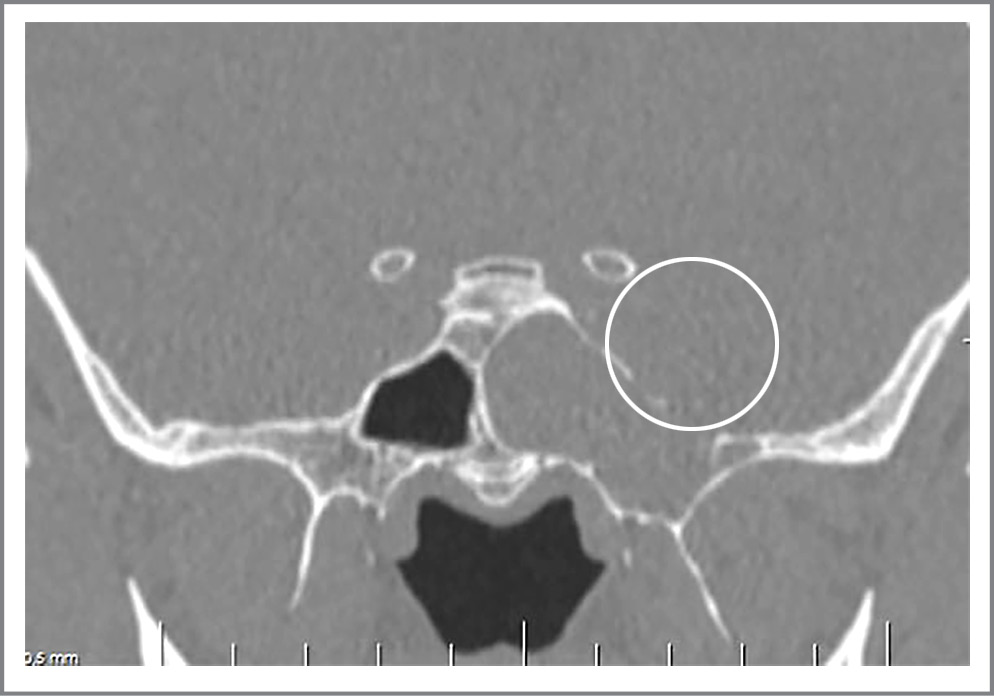

Перед операцией проведена КТ-цистернография, которая выявила наличие дефекта основания черепа: в области турецкого седла (рис. 3).

Рис. 3. КТ-цистернография. Фронтальная проекция. Дефект в области турецкого седла.

Анамнез заболевания: считает себя больным с августа 2019 г., когда без явной причины появились жидкие выделения из левой половины носа. Консультировался у оториноларинголога по месту жительства, поставлен диагноз «назальная ликворея». Проходил лечение в ФГАУ «НМИЦН им. акад. Н.Н. Бурденко», где выполнена операция «эндоскопическая эндоназальная пластика дефекта основания черепа в области латерального кармана клиновидной пазухи справа». После операции чувствовал себя хорошо, выделения отсутствовали. Однако через 3 мес после операции вновь отметил прозрачные выделения из носа справа при наклоне головы. Отмечал кашель по ночам, головные боли. С этими жалобами обратился в ФГАУ «НМИЦН им. акад. Н.Н. Бурденко» для повторного хирургического лечения. При осмотре оториноларинголога: профузная назальная ликворея; дефект в области латерального кармана клиновидной пазухи справа (рис. 5).

Рис. 5. КТ головного мозга, фронтальная проекция. Дефект основания черепа в области латерального кармана клиновидной пазухи слева.